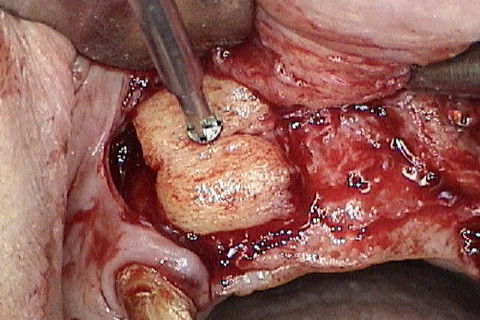

Mostrando o defeito ósseo após rebatimento do retalho

Bloco ósseo cortico-medular

Bloco ósseo sendo fixado com o auxilio de pinça porta-enxerto

Blocos ósseos fixados. Os espaços entre os blocos foram preenchidos com osso particulado. Na verdade deveriam ser utilizados 2 blocos nessa região e não somente 1 como foi utilizado.